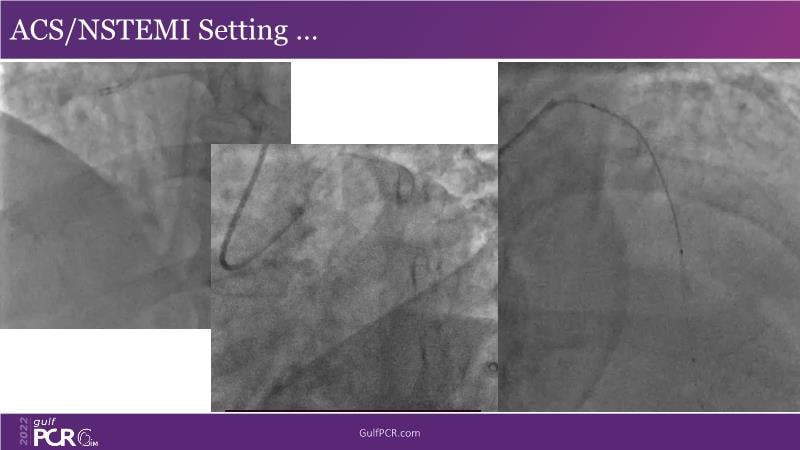

Optimal PCI in patient with long calcified lesion

In this session, follow a LIVE case from the Chest Diseases Hospital in Kuwait and learn what the best strategy is to treat patients who present with a very long calcified coronary artery lesion, as well as how to select the best device and which different types of stents can be used.